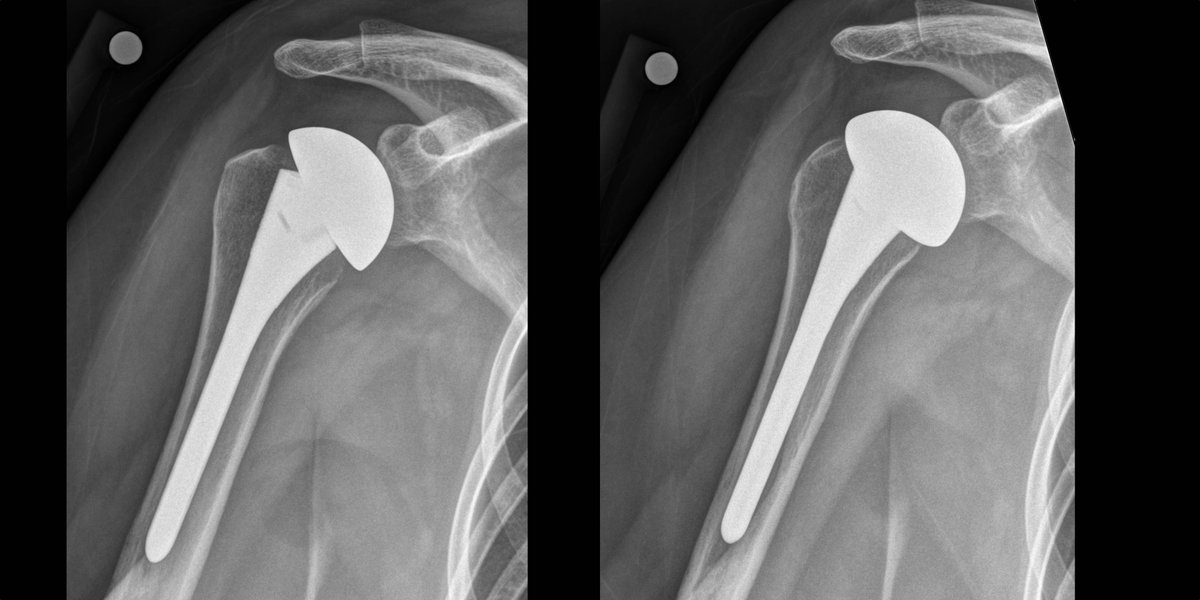

- Algorithm for Anatomic Total Shoulder Arthroplasty

Courtesy: Dr Sarav Shah MD, FAAOS New England Baptist Hospital, Boston, MA